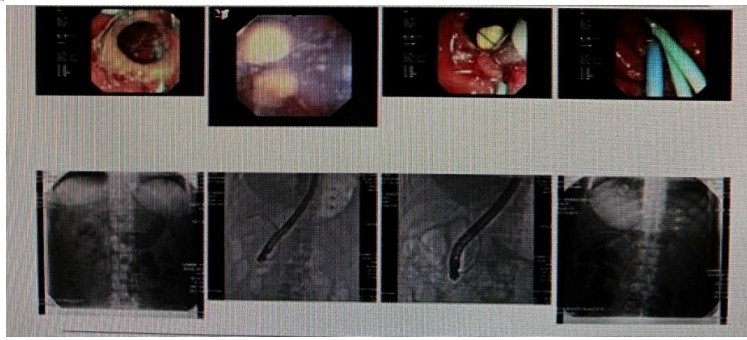

消化內(nèi)科肝病亞專科團(tuán)隊(duì)詳細(xì)討論,分析患者情況后,取消了周女士的肝穿刺活檢檢查,建議患者先行超聲胃鏡下膽胰掃查。在內(nèi)鏡醫(yī)師第三只眼——超聲胃鏡的掃查下,發(fā)現(xiàn)引起周女士肝功能受損的罪魁禍?zhǔn)?/span>原來是膽總管末端結(jié)石!伍友興主任醫(yī)師帶領(lǐng)團(tuán)隊(duì)給予患者行ERCP下取石后,周女士未再出現(xiàn)腹痛,肝功能恢復(fù)正常。

無獨(dú)有偶,劉先生也為反復(fù)出現(xiàn)肝功能受損到多家醫(yī)院就診檢查,未能找到原因,來到衡陽市中心醫(yī)院消化內(nèi)科就診,希望能在肝穿刺活檢下得出病因。在行肝穿刺活檢之前,醫(yī)生建議劉先生行超聲胃鏡膽胰掃查,發(fā)現(xiàn)引起劉先生反復(fù)肝功能受損原因,亦是膽總管結(jié)石引起,在ERCP術(shù)取石術(shù)后,患者肝功能恢復(fù)正常,未再出現(xiàn)異常情況。

張丹霞主任醫(yī)師介紹,超聲內(nèi)鏡通過胃十二指腸自然腔道,可以將探頭貼近相應(yīng)的位置,近距離的觀察胰腺及膽道系統(tǒng),準(zhǔn)確捕捉到直徑小于5毫米的胰腺異常病灶及膽道系統(tǒng)病灶。而體表B超常受皮膚、脂肪或腸道氣體干擾。CT或磁共振檢查只能提供靜態(tài)圖像,且對(duì)膽胰管陰性結(jié)石或是未引起明顯膽管梗阻性的結(jié)石檢查有局限性,因此對(duì)于有輕微腹痛合并肝功能受損的患者,建議常規(guī)行超聲胃鏡下膽胰掃查。超聲胃鏡、腹部彩超、腹部CT、腹部MRI同為診斷膽管細(xì)微病變的四架馬車,在膽總管結(jié)石診斷方面,超聲胃鏡膽胰掃查同ERCP一樣,是敏感性高、特異性強(qiáng)的診斷方法。超聲胃鏡發(fā)現(xiàn)可疑病變,可以完成穿刺活檢,還可行囊腫穿刺引流、膽管減壓、消融術(shù)等。